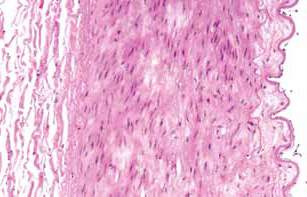

A sectional view of the arterial wall. On the right aortic pulse wave velocity (aPWV) is an inde-is the intima, topped by a layer of cells called the pendent predictor of arterial stiffness and cardio-endothelium. The endothelium acts as a barrier to vascular disease and death.

prevent certain substances from entering the vessel wall. In the center, the media is composed of

As the walls of the large arteries become stiffer,

smooth muscle cells and a network of fibrous pro-

diastolic blood pressure tends to drop and systolic

teins. The outermost layer, the adventitia, is com-blood pressure rises. The difference between these

posed of connective tissue.